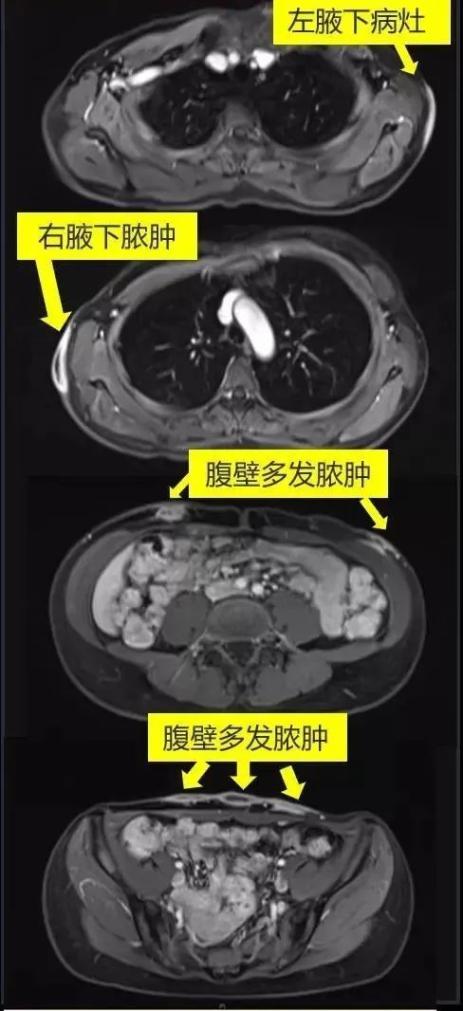

入院后,医生赶紧为小美安排了相关检查,这一查,发现小美“埋蛋白线”处的皮下已有多处脓肿形成,其中最深之处已侵犯到了肌肉层。医生迅速为她抽取了一处病灶内的脓液送微生物检查,根据初步的培养结果,经验性使用了联合抗生素治疗。并为小美请来整形外科专家会诊,进行了多处脓肿的切开引流手术。经验丰富的手术医生非常乐意听取感染科医生的意见,术中仔细留取了各个部位的脓液和组织,进行的微生物学检查。